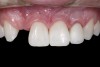

(1.) Initial presentation. Note midline shift to right, missing right lateral incisor, and diminutive left lateral incisor in crossbite.

Figure 1

A 14-year-old patient presented to the office with his mother (Figure 1). His chief complaint involved the large spaces between the teeth created by his missing right maxillary lateral incisor and his small left maxillary lateral incisor. He desired to replace the missing tooth with an implant and create a beautiful smile. Upon examination, he was found to have a class I canine and molar relationship, but because he had a tooth size/arch size discrepancy and space distal to the right central incisor, the remaining incisors had drifted to the right. The left maxillary lateral incisor was peg-shaped and in a cross bite position. Studies have shown a clear association between congenitally missing teeth and reduced tooth size.59-62 Because he was only 14-years-old at the time and could not have implants placed until the cessation of growth (somewhere in the vicinity of 22 years old), he was sent to the orthodontist for alignment of the teeth.16,17 After 2 years of orthodontics, the appliances were removed, and his tooth coloration was improved using carbamide peroxide bleaching (Figure 2). Because some form of provisional needed to be placed until he was finished growing, a double-wing metal resin-bonded bridge was chosen. As discussed earlier, this is the ideal transitional prosthesis for patients that have congenitally missing maxillary lateral incisors. The benefits of this type of prosthesis include its ability to be removed and rebonded during the surgical phase of treatment and its ability to retain the roots in their proper position after orthodontic treatment.16 The final plan for the patient was to increase the width of the central and the maxillary left lateral incisor, utilizing porcelain laminate veneers to achieve the appropriate width/length ratio of 80%. A wax-up was created to idealize tooth size, a putty matrix was made from the wax-up to facilitate bonding of the incisors, and a non-precious, double-wing metal resin-bonded bridge was fabricated for lateral incisor replacement. Once the teeth were bonded to ideal size, the “Maryland Bridge” was fabricated from a polyvinyl arch impression with the newly bonded teeth (Figure 3). The metal frame was cast from a non-precious alloy to allow for fabrication of a very thin frame and to create a better surface for bonding. After sandblasting the internal aspect of the frame with CoJet™ silica (3M ESPE), accomplishing salinization, and executing cementation with a dual-cure resin cement, a fairly good adhesion to the frame was anticipated.29 The enamel surface was etched with phosphoric acid for 30 seconds, the primer (Single Bond Plus, 3M ESPE) was applied to both the internal surface of the sandblasted framework and the etched enamel, and the bridge was cemented with RelyX™ ARC (3M Espe) dual-cured resin cement (Figure 4 and Figure 5).